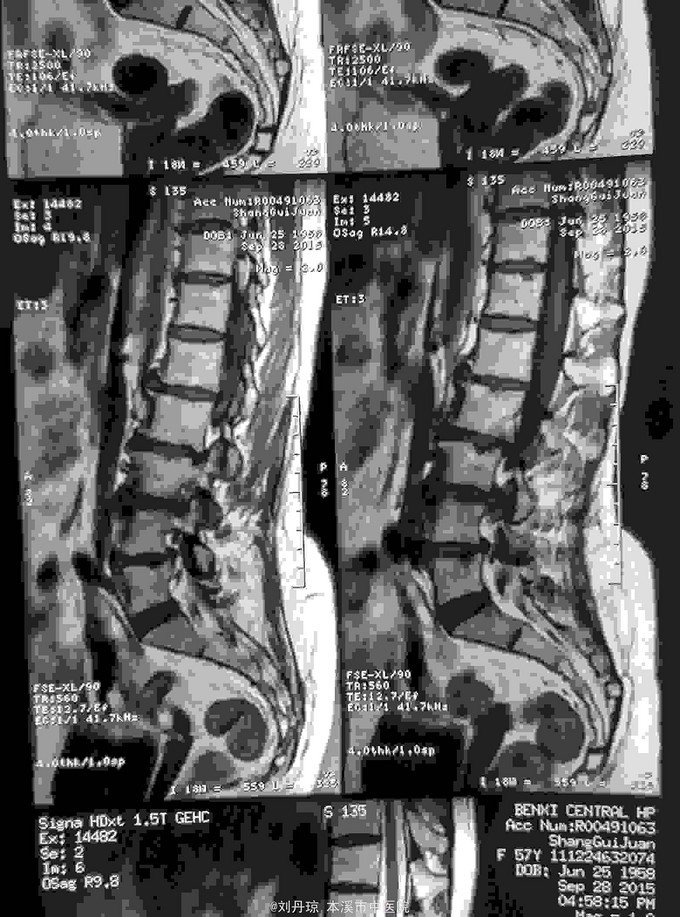

腰部疼痛伴右下肢放射痛麻木感半年,加重2月。患者半年前劳累后感到腰部疼痛伴右下肢放射痛麻木感,近2月病情加重来诊。

查体:L1—S1棘突右旁压痛阳性。直腿抬高实验左70度,右40度。 直腿抬高加强实验左侧阴性,右侧阳性。腰椎功能障碍。 辅查:CT: L1—S1椎间盘突出。

诊断:腰椎间盘突出症 治疗:针灸、雷火灸、中药熏药治疗、小针刀治疗、骶管注射治疗、营养神经药物治疗、脱水药物治疗,当归地黄饮加味。

随访1年。腰为肾之府,故腰椎间盘突出症一病与肾关系最为密切。肾主骨,生髓、通于脑。这从生理上说明脊柱的生理、病理与肾有着必然的联系。